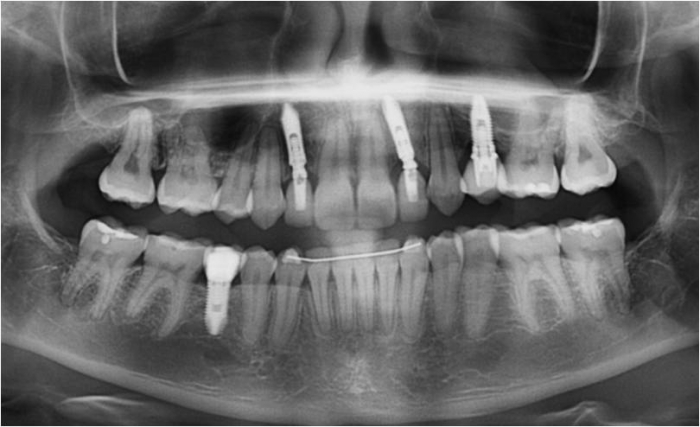

Raio X inicial

Imagem após extrações de dentes decíduos e instalação de um implante